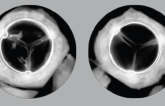

Solid Durability Seen With Surgical Resilia Tissue Aortic Valve